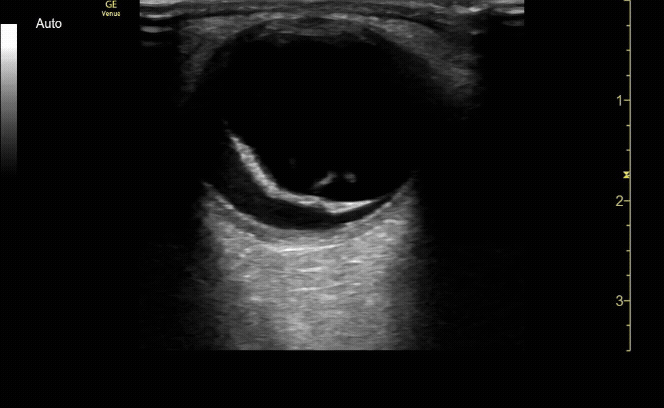

Mac off retinal detachment. Retina tethered at optic nerve.

c/o Melissa Hoshizaki, MD